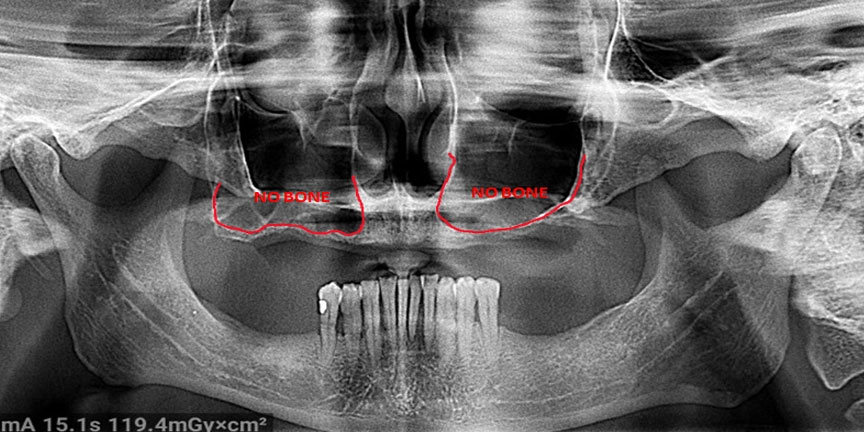

Expertise with Complex Cases: We handle challenging cases that other providers may struggle with, offering solutions where others cannot.